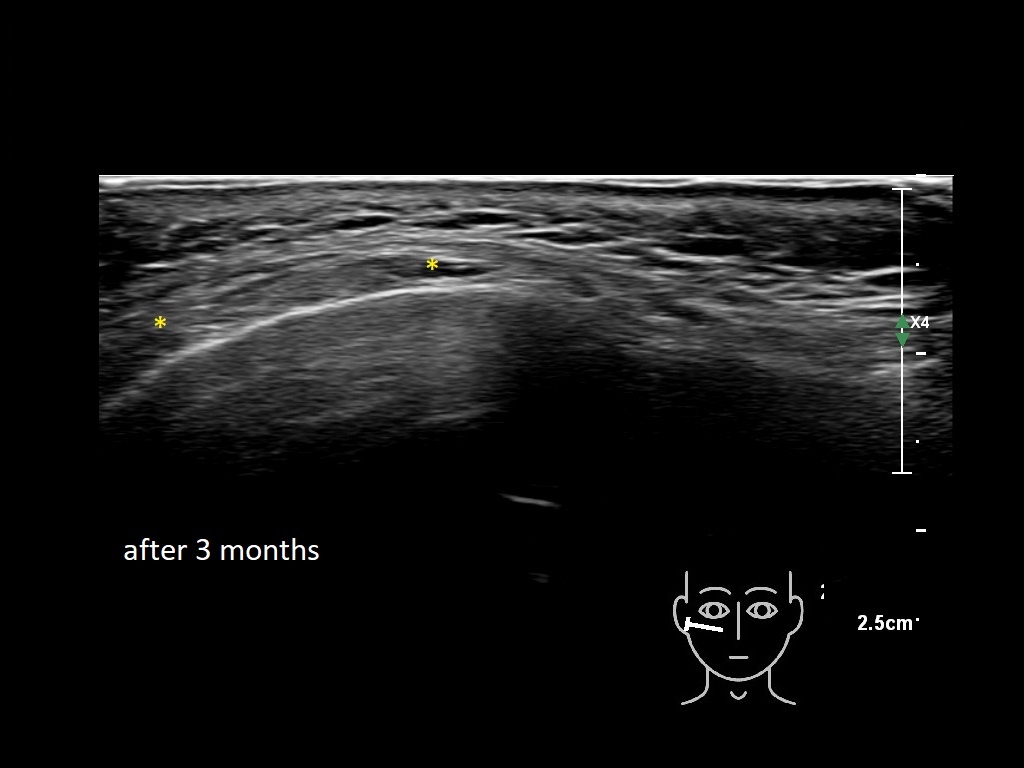

Draw in the image on the right where the fillers are located. To check if your answer is correct, please click on the secondary image.